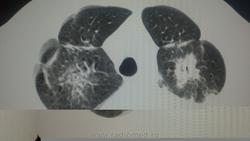

Мужчина 60 лет. Заболел остро около месяца назад с подъема температуры до 38, появился сухой кашель, слабость. Лечится в пульмонологии с диагнозом двусторонняя внебольничная пневмония. В анализах от 14.01 Hb147 , L7,9   СОЭ 22  от 16.01 Hb 144, L8,1   соэ 27   от 20.01 Hb 138 L9,0 соэ40

УЗИ плевральных полостей двусторонний гидроторакс.

В средостении единичные увеличенные до 14 мм. в поперечнике лимфоузлы паратрахеальной группы, некоторые с признаками инволюции. Дайкомы загрузить не получится, на работе интернет никакой, грузится до послезавтра будет.

Если по длиннику до 18,5 мм. увеличены паратрахеальные справа. Лимфоузлы с признаками инволюции- это я имела ввиду жировую перестройку.

Правые верхние паратрахеальные.

имхо: с учётом всей имющейся информации, предварительно предложил бы дифференциально-диагностический ряд:

1.Двухсторонняя полисегментраная плевропневмония, возможно вирусной этиологии.

2. Пневмония при острой ревматической атаке, поражения  с 2-х сторон относительно симмеричны, и напоминают " ревматическую бабочку".

3. С учётом поражения лимфатичских узлов паратрахеальной группы и острого начала не исключал бы версию лимфомы Ходжкина (лимфогранулематоза).

К сожалению да, т.к. отсутствует эффект от месячного лечения. По сравнению с предоставленными мне  Р-граммами динамики нет совершенно. МСКТ-исследование выполнено 23.01.14.